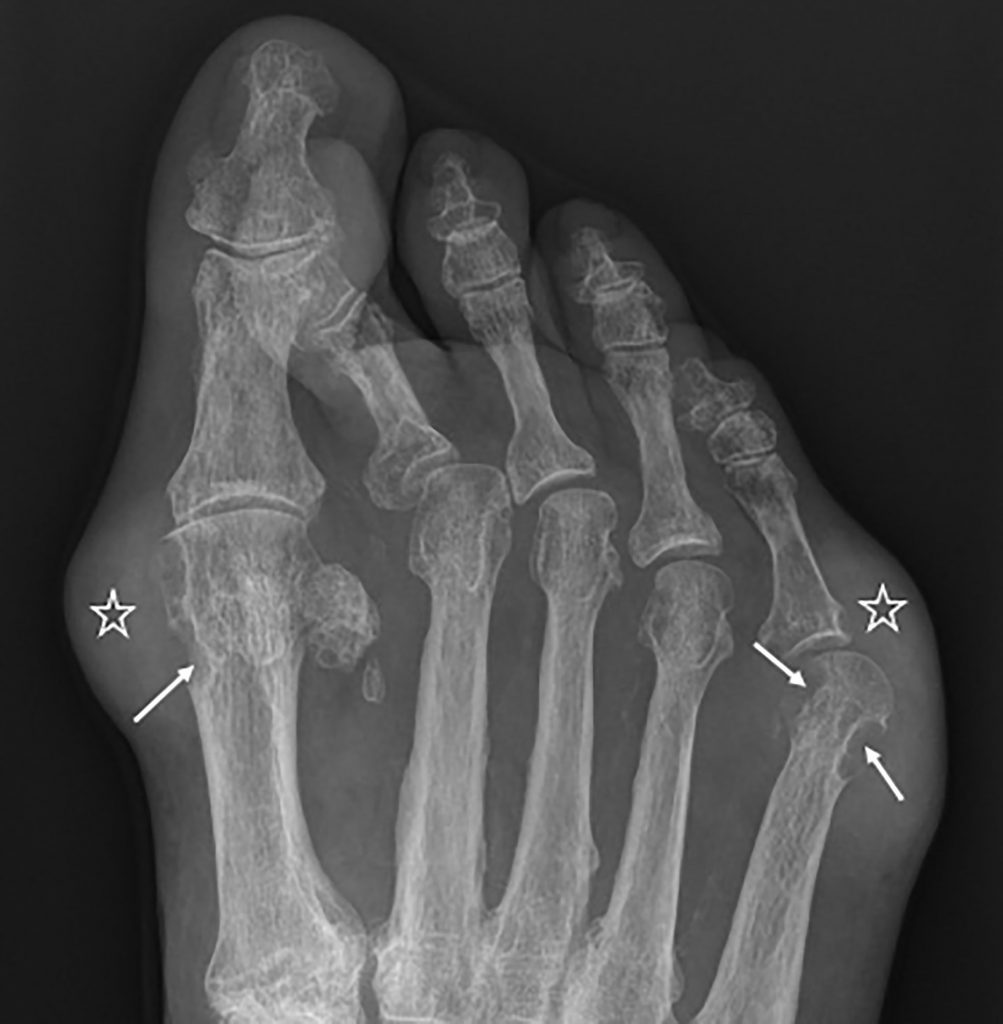

Atteinte typique de la 1re articulation métatarsophalangienne.

- Dépôts denses, en amas, des tissus mous appelés « tophus ».

Érosions para-articulaires, à distance de l’interligne, avec aspect en « hallebarde » (figure 75.2).

Fig. 75.2 Goutte.

Radiographie du pied droit de face montrant des érosions para-articulaires avec aspect en « hallebarde » (flèches) et des tophus péri-articulaires sous forme de dépôts denses en amas des parties molles (étoiles). L’interligne articulaire est préservé.

Source : CERF, CNEBMN, 2022.